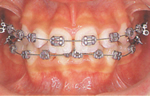

(2)

上下の歯が計画どおりに動いて、次第に正常なかみ合わせになると最終段階で仕上げの治療をします。

(3)

動的な治療が完了すると矯正装置をはずし、保定に入ります